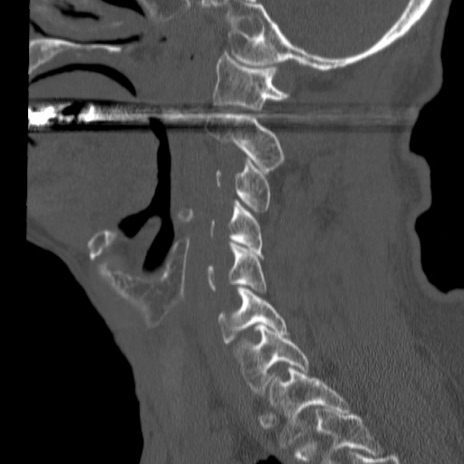

症例46 頚椎CT(矢状断像)

【症例】80歳代男性

【主訴】両側頚部〜上肢のしびれ

【現病歴】昨日、自宅内で転倒、その後より上記症状あり。意識障害なし。

【身体所見】両側上肢のallodynia(熱痛覚過敏)あり。MMTおよびDTRは正確な所見取れず。両上肢の挙上はなんとか可能。

異常所見と診断は?